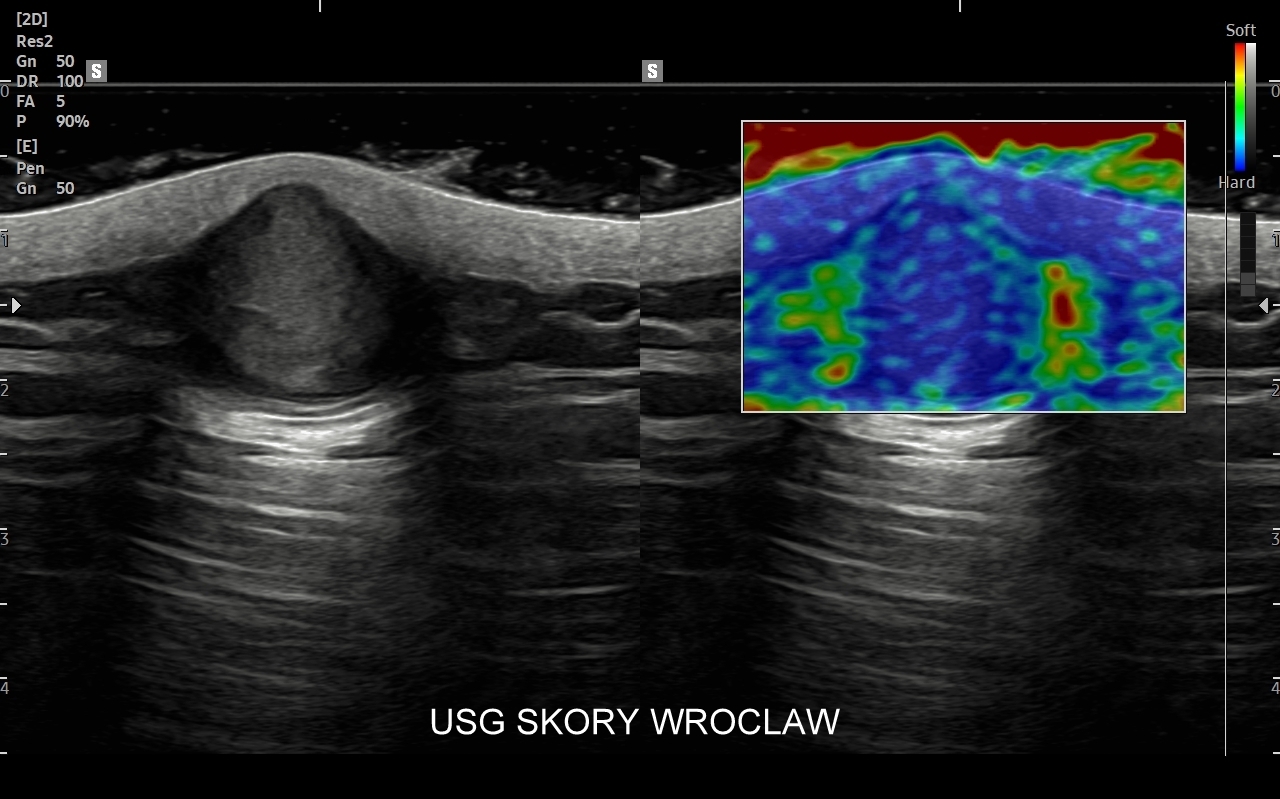

• badania Elastoscan guzów i tkanek,

Dr Tomasz Szczepański zajmuje się kompleksową opieką medyczną nad swoimi Pacjentami. W ramach Interdyscyplinarnej Pracowni USG Wrocław wykonuje szereg uzupełniających się badań, zarówno klasycznych, jak USG jamy brzusznej, USG tarczycy, USG piersi, pełen zakres diagnostyki USG Doppler, jak i wysokospecjalistycznych, w tym badania multiparametryczne (MPUS), badania USG z kontrastem (CEUS), ocena przetok dializacyjnych, badania USG Doppler przepływów nerkowych, czy badania USG twarzy